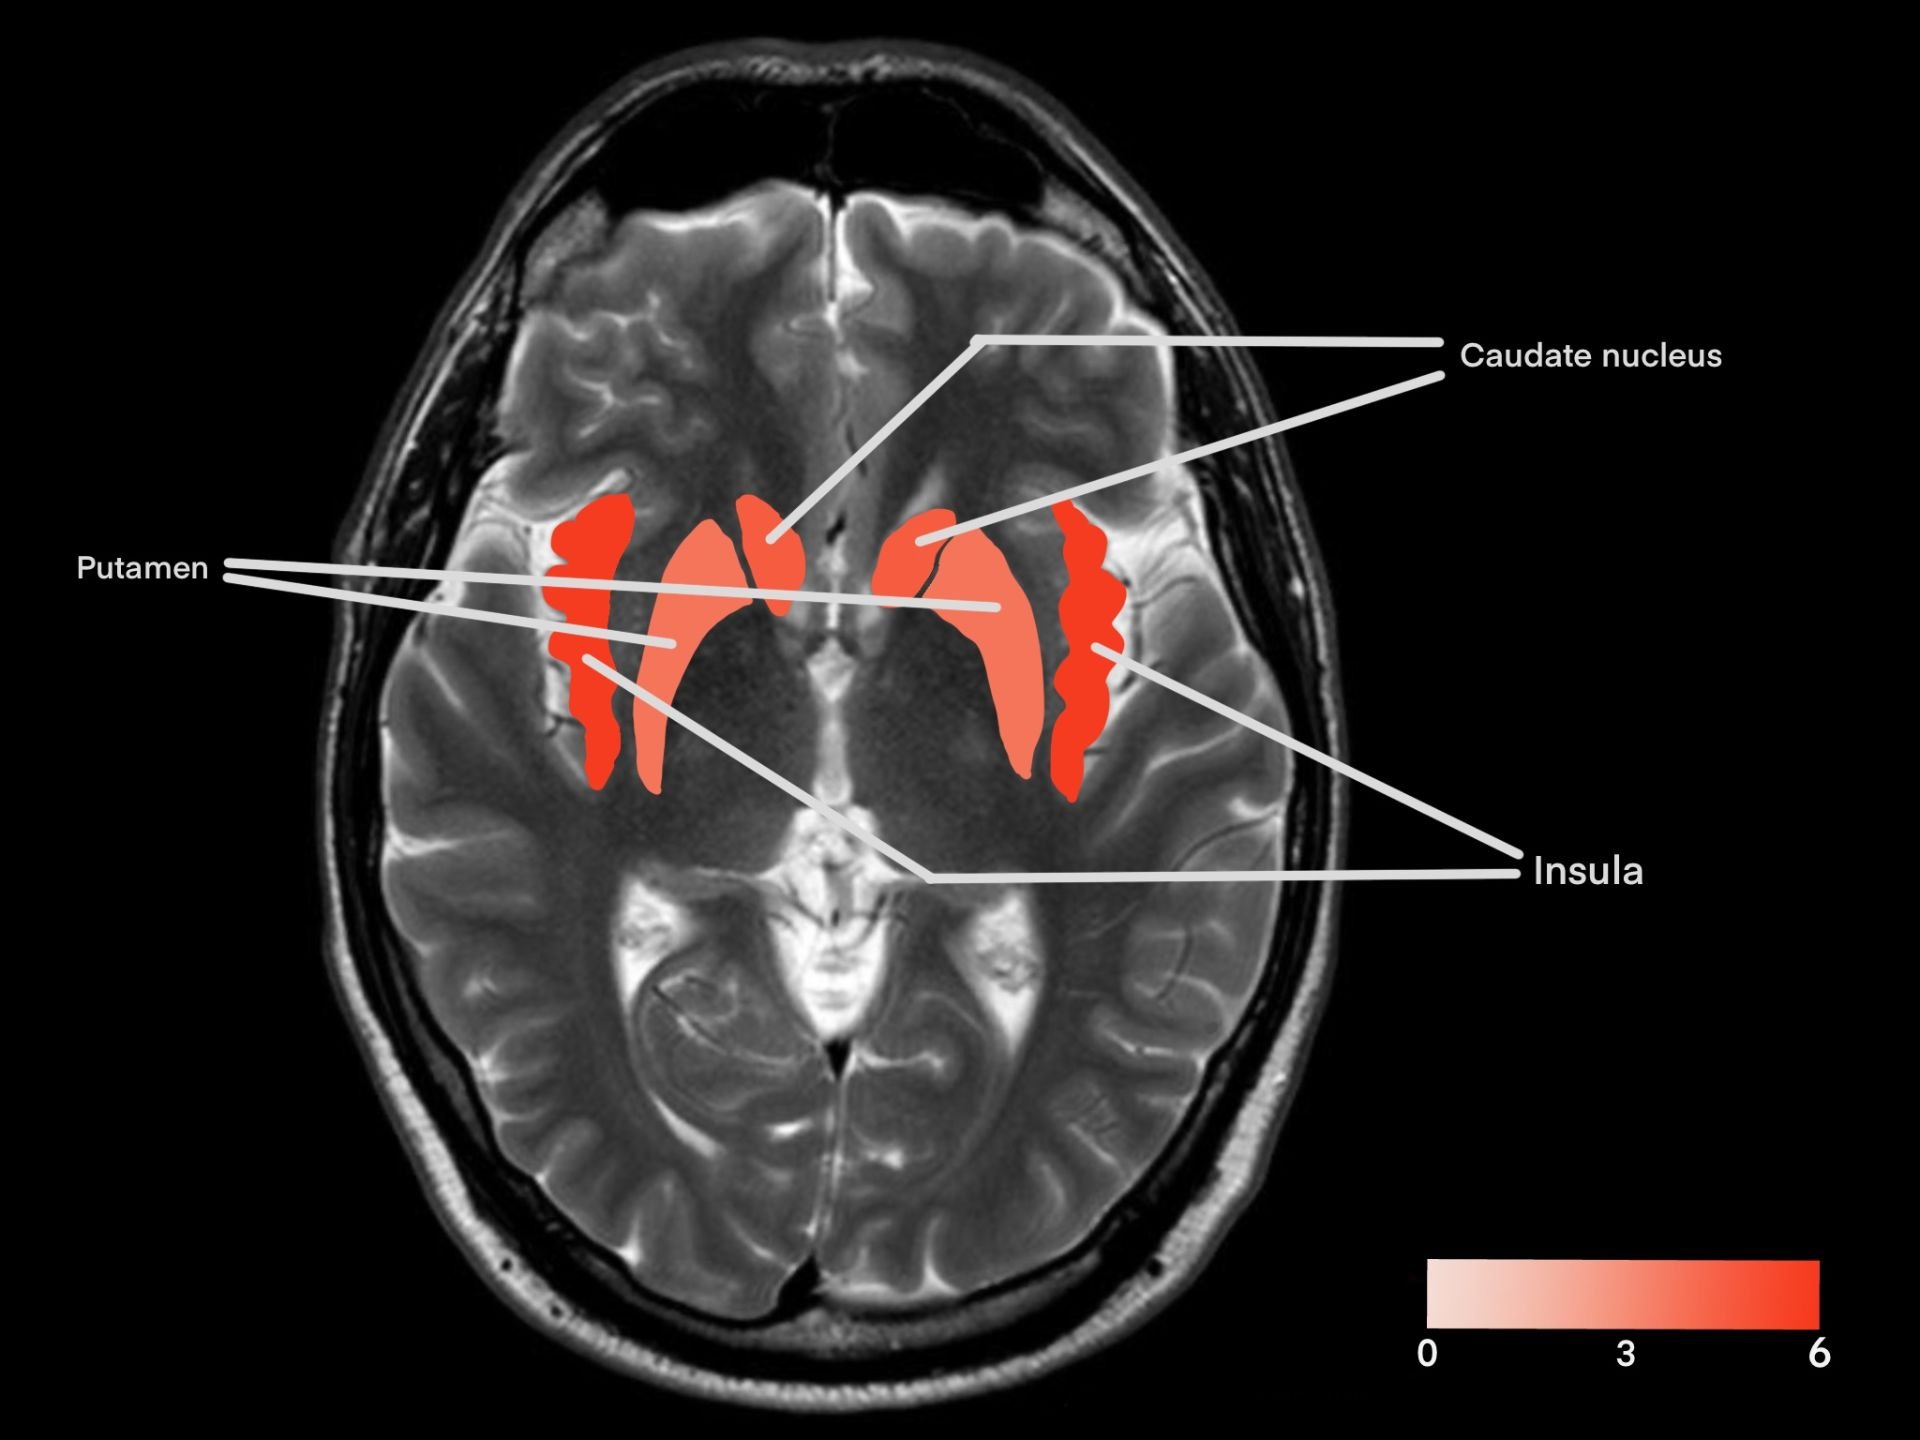

Across the analyzed papers, several regions were consistently reported as activated or deactivated during romantic love. For example, the insular cortex (also known as the insula) was found to be activated in six out of eleven studies analyzed. The anterior cingulate cortex, in proximity to the insula, was also observed to have an activation signal during romantic love in four studies. Also analyzed as activating during romantic love was the dorsal striatum, the area including the caudate nucleus and putamen, which had reported activation five times and four times respectively across eleven papers, particularly in those that had asked participants to view images of the person they love romantically versus a control. Another region that was discovered to activate during romantic love was the ventral tegmental area (VTA), activating in four out of eleven studies gathered. Lastly, there is the amygdala, which was seen to both activate and deactivate in certain contexts of romantic love, depending on the experiment, reported in five studies out of the total eleven. Other regions of the brain also reported BOLD signals (thalamus, etc.); however, they were not as consistent across the eleven studies as the aforementioned regions were. Most regions that reported activation in the studies analyzed are included in the figure or table below.

Figure 2A/2B. Frequency of reported activation across 11 fMRI studies examining romantic love. Color intensity represents the number of studies reporting activation in each region.

Within the same reward pathway as the VTA is the caudate nucleus, which is involved in goal-directed reward learning and positive reinforcement (Haruno et al., 2004), thereby reinforcing behaviours associated with reward outcomes. The caudate nucleus was observed to activate in response to exposure to the participant’s beloved, whether anticipating viewing an image of them, actually viewing their image, or thinking of experiences that they shared (Acevedo et al., 2012; Aron et al., 2005; Bartels & Zeki, 2004; Langeslag et al., 2014). For example, in Langeslag et al. (2014), the caudate nucleus in participants had a significantly greater activation signal when anticipating seeing an image of their beloved compared to waiting for an image of their friend or a stranger. Within the same circuit as the caudate (together being the dorsal striatum), the putamen has been associated with stimulus-response learning and habit reinforcement (Ersche et al., 2021). Studies examining romantic love also reported putamen activation, such as in the previously mentioned experiment in Langeslag et al., during anticipation of receiving a compliment. Together, activation of the caudate nucleus and putamen suggests that romantic love engages dorsal striatal circuitry involved in both goal-directed behaviour and habit reinforcement, potentially supporting the persistence of attachment-like behaviours over time.

A region of the brain that is often associated with emotional response is the insular cortex (also known as the insula), which is involved in processing internal functions like heartbeat and breathing, integrating bodily states into emotions like fear, disgust, or, in this case, romantic love (Uddin et al., 2017; Zhang et al., 2024). The insula was the most frequently activated region across the analyzed studies, particularly in experiments where participants were asked to report their personal feelings after the experiment (Acevedo et al., 2012; Bartels & Zeki, 2004; Rinne et al., 2024). For example, in Ebisch et al. (2014), participants were either caressed with a rubber ball (for control) or the hand of their beloved. These findings indicate that insular activity was increased during the trial using the hand but not the ball. This suggests that the physical caress associated with their beloved contributed to the increased activation, supporting the current consensus on its function with bodily monitoring and emotion. This suggests that romantic love is not simply abstract cognition, but also involves bodily states.